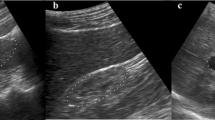

Typically, the acquired renal ultrasound image includes a course of speckle noises. This paper primarily investigates an approach for the detection of renal calculi by processing those raw US images with the help of a meta-heuristic SVM classifier. One of the major downsides of involving Ultrasound images in medical analysis is the prevalence of Speckle Noises. An Adaptive Mean Median Filter approach has been introduced in the work to get rid of the speckle noises to the maximum extent ever in the literature. Segmentation is performed by employing conventional K-Means and GLCM features were extracted for classification using a meta-heuristic SVM classifier. The proposed methodology investigates with a Real-time Acquired Dataset of Mithra Scans, Tamilnadu, India comprises of 250 clinical Ultra-Sound Kidney Images of which 150 are having Calculi and the rest are Healthy. With the experimental results, the proposed meta-heuristic SVM classifier have performed better in noisy images while comparing with other conventional methods considered in the literature. It exhibits an Accuracy of 98.8% with a FAR rate of 1.8 for FRR as high as 3.3. The results clearly proposed that the novel AMM-PSO-SVM could be a promising technique for object or foreign body detection in a medical imaging application that uses ultrasound imaging.